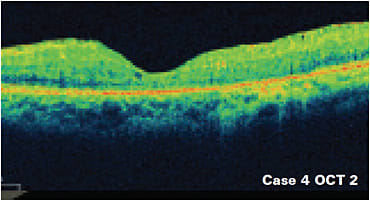

OCT and OCT angiography (OCTA) have dramatically improved early detection and care of diabetic retinopathy and maculopathy. OCT allows for the early identification and management of DME, rather than the presence of clinically significant macular edema, a diagnosis made by macula slit lamp examination. Currently, DME is categorized as center-involved versus non-center-involved based on spectral domain OCT. Center-involved DME is characterized by loss of foveal contour, cystoid macula edema (CME) involving the center of the fovea, neurosensory detachment involving the center of the fovea and increased central subfield thickness as shown in case 4. Non-center-involved DME is characterized by retinal thickening and/or cystic spaces not directly involving the center of the macula.

Case 4: 57-year-old male with center-involved DME of the left eye; note improvement status post anti-VEGF therapy